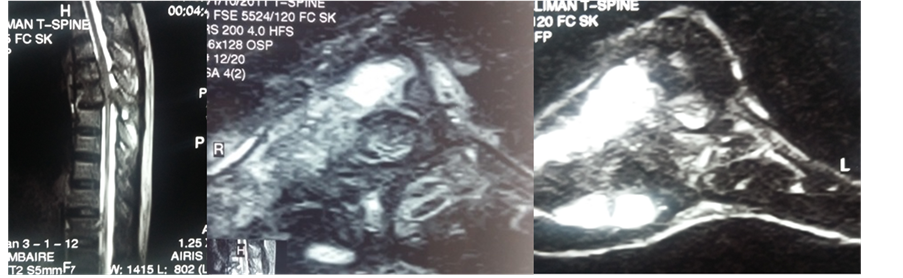

Mr. YKK, a 39-year-old ivorian, HIV immunocompetent and no other medical history, presented in February 2011 with progressive deterioration of his general health, thoracic rachialgia and intercostal pain, low back pain and lower limbs heaviness. Clinical examination revealed a slow thoracic spinal cord compression syndrome with a slight deficit and a 4/5 muscle strength of the lower limbs, a lumbosacral spine syndrome. CT scan and MRI of the thoracic spine showed lysis of T4, T5, T6 and T7 vertebrae, an epiduritis and paravertebral abscesses (Figure 1). CT scan of the lumbar spine demonstrated osteolysis of the left iliac wing with skin invasion. This lesion invaded the sacrum and the body of L5 (Figure 1). MRI of the lumbar spine showed no nerve root compression (Figure 1). Several diagnosis hypotheses were suggested: a multifocal tuberculosis (vertebral and iliac) or infection with other microorganisms (bacterial or parasitic), vertebral and iliac metastasis. A thoraco-abdo- minopelvic CT scan to search for a primary cancer was non-conclusive. An iliac bone biopsy performed revealed a giant cell granulomatous tissue, with large ovoid yeast consistent with Histoplasma duboisii. Histopathological examination of osseous biopsy concluded bone histoplasmosis with multiple localization of Histoplasma duboisii. The patient was treated with ketoconazole 400 mg daily for six months. Spinal decompressive surgery was not performed. Our conservative approach was based on clinical grounds of minimal neurological disorders and normal spine morphology. Following antifungal treatment the patient had satisfying clinical and radiological outcome. After three years follow-up, the clinical course was uneventful. The patient had neither symptoms of spinal cord compression nor signs of further localizations.

Figure 1. Sagittal view of thoracic CT scan showing osteolytic lesion T4, T5, T6 and T7 vertebral (a) at the sacrum, (b) thoracic frontal view (T5 to T7) lumbar frontal view osteolyic lesion and abcess (e) axial view with osteolytic in vertebral extending to pleural (f), axial view ilac osteolytic lesion (g) T1 weighted sagittal view showing spinal cord compression associated to vertebral body lesion (h) T2 weighed MRI on sagittal view, showing T4 - T7 epiduritis and paravertebral abscesses which is hyposignal (i) and (j). Histological examination showing Histoplasma duboisii in giant cell (Schiff periodic acid coloration ×100 (k).